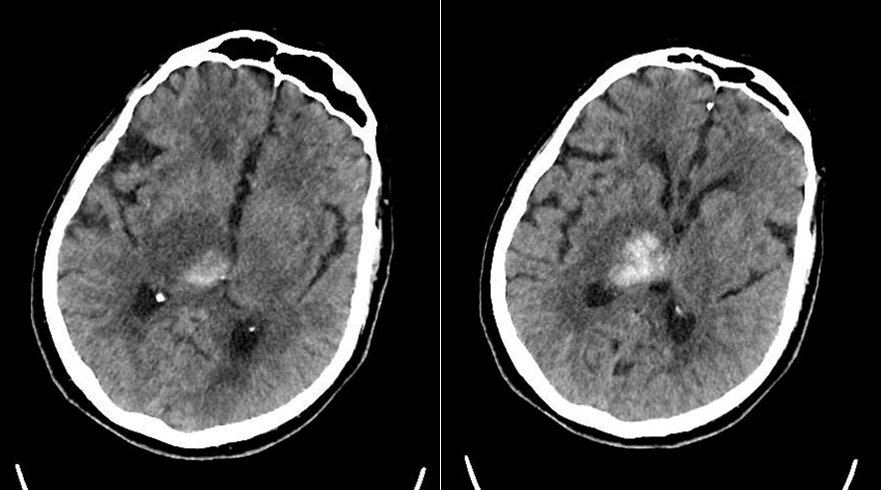

Le type d’hémianopsie est très important car il permet de localiser une atteinte neurologique, en connaissant le trajet des voies optiques.

Figure d’après le Collège des enseignants de neurologie (CEN). Altération aiguë de la vision.

Cette question supposait d’avoir bien en tête le schéma des voies optiques, et d’avoir des repères sur les principaux territoires vasculaires cérébraux et l’atteinte clinique associée. Il bien mentionné par le CEN que l’hémianopsie latérale homonyme gauche peut se voir dans un AVC sylvien superficiel droit.

Tableau d’après le Collège des enseignants de neurologie. Altération aiguë de la vision.